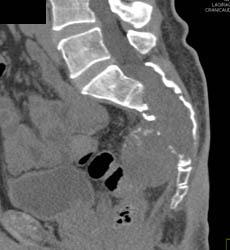

Chordoma